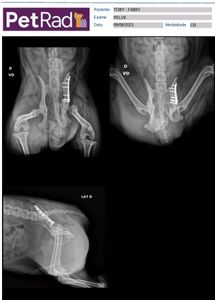

Hoje compartilhamos com vocês a história do nosso fiel amigo de quatro patas, o Tobi. Ele sofreu um acidente trágico e foi atropelado, resultando em ferimentos graves que exigiram uma cirurgia emergencial. A cirurgia salvou sua vida, mas também trouxe um ônus financeiro pesado, com custos que já ultrapassaram os 5.000 reais, incluindo gastos com clínica, medicamentos e acompanhamento médico.